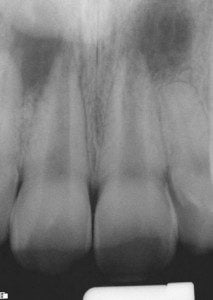

end-case-3-b